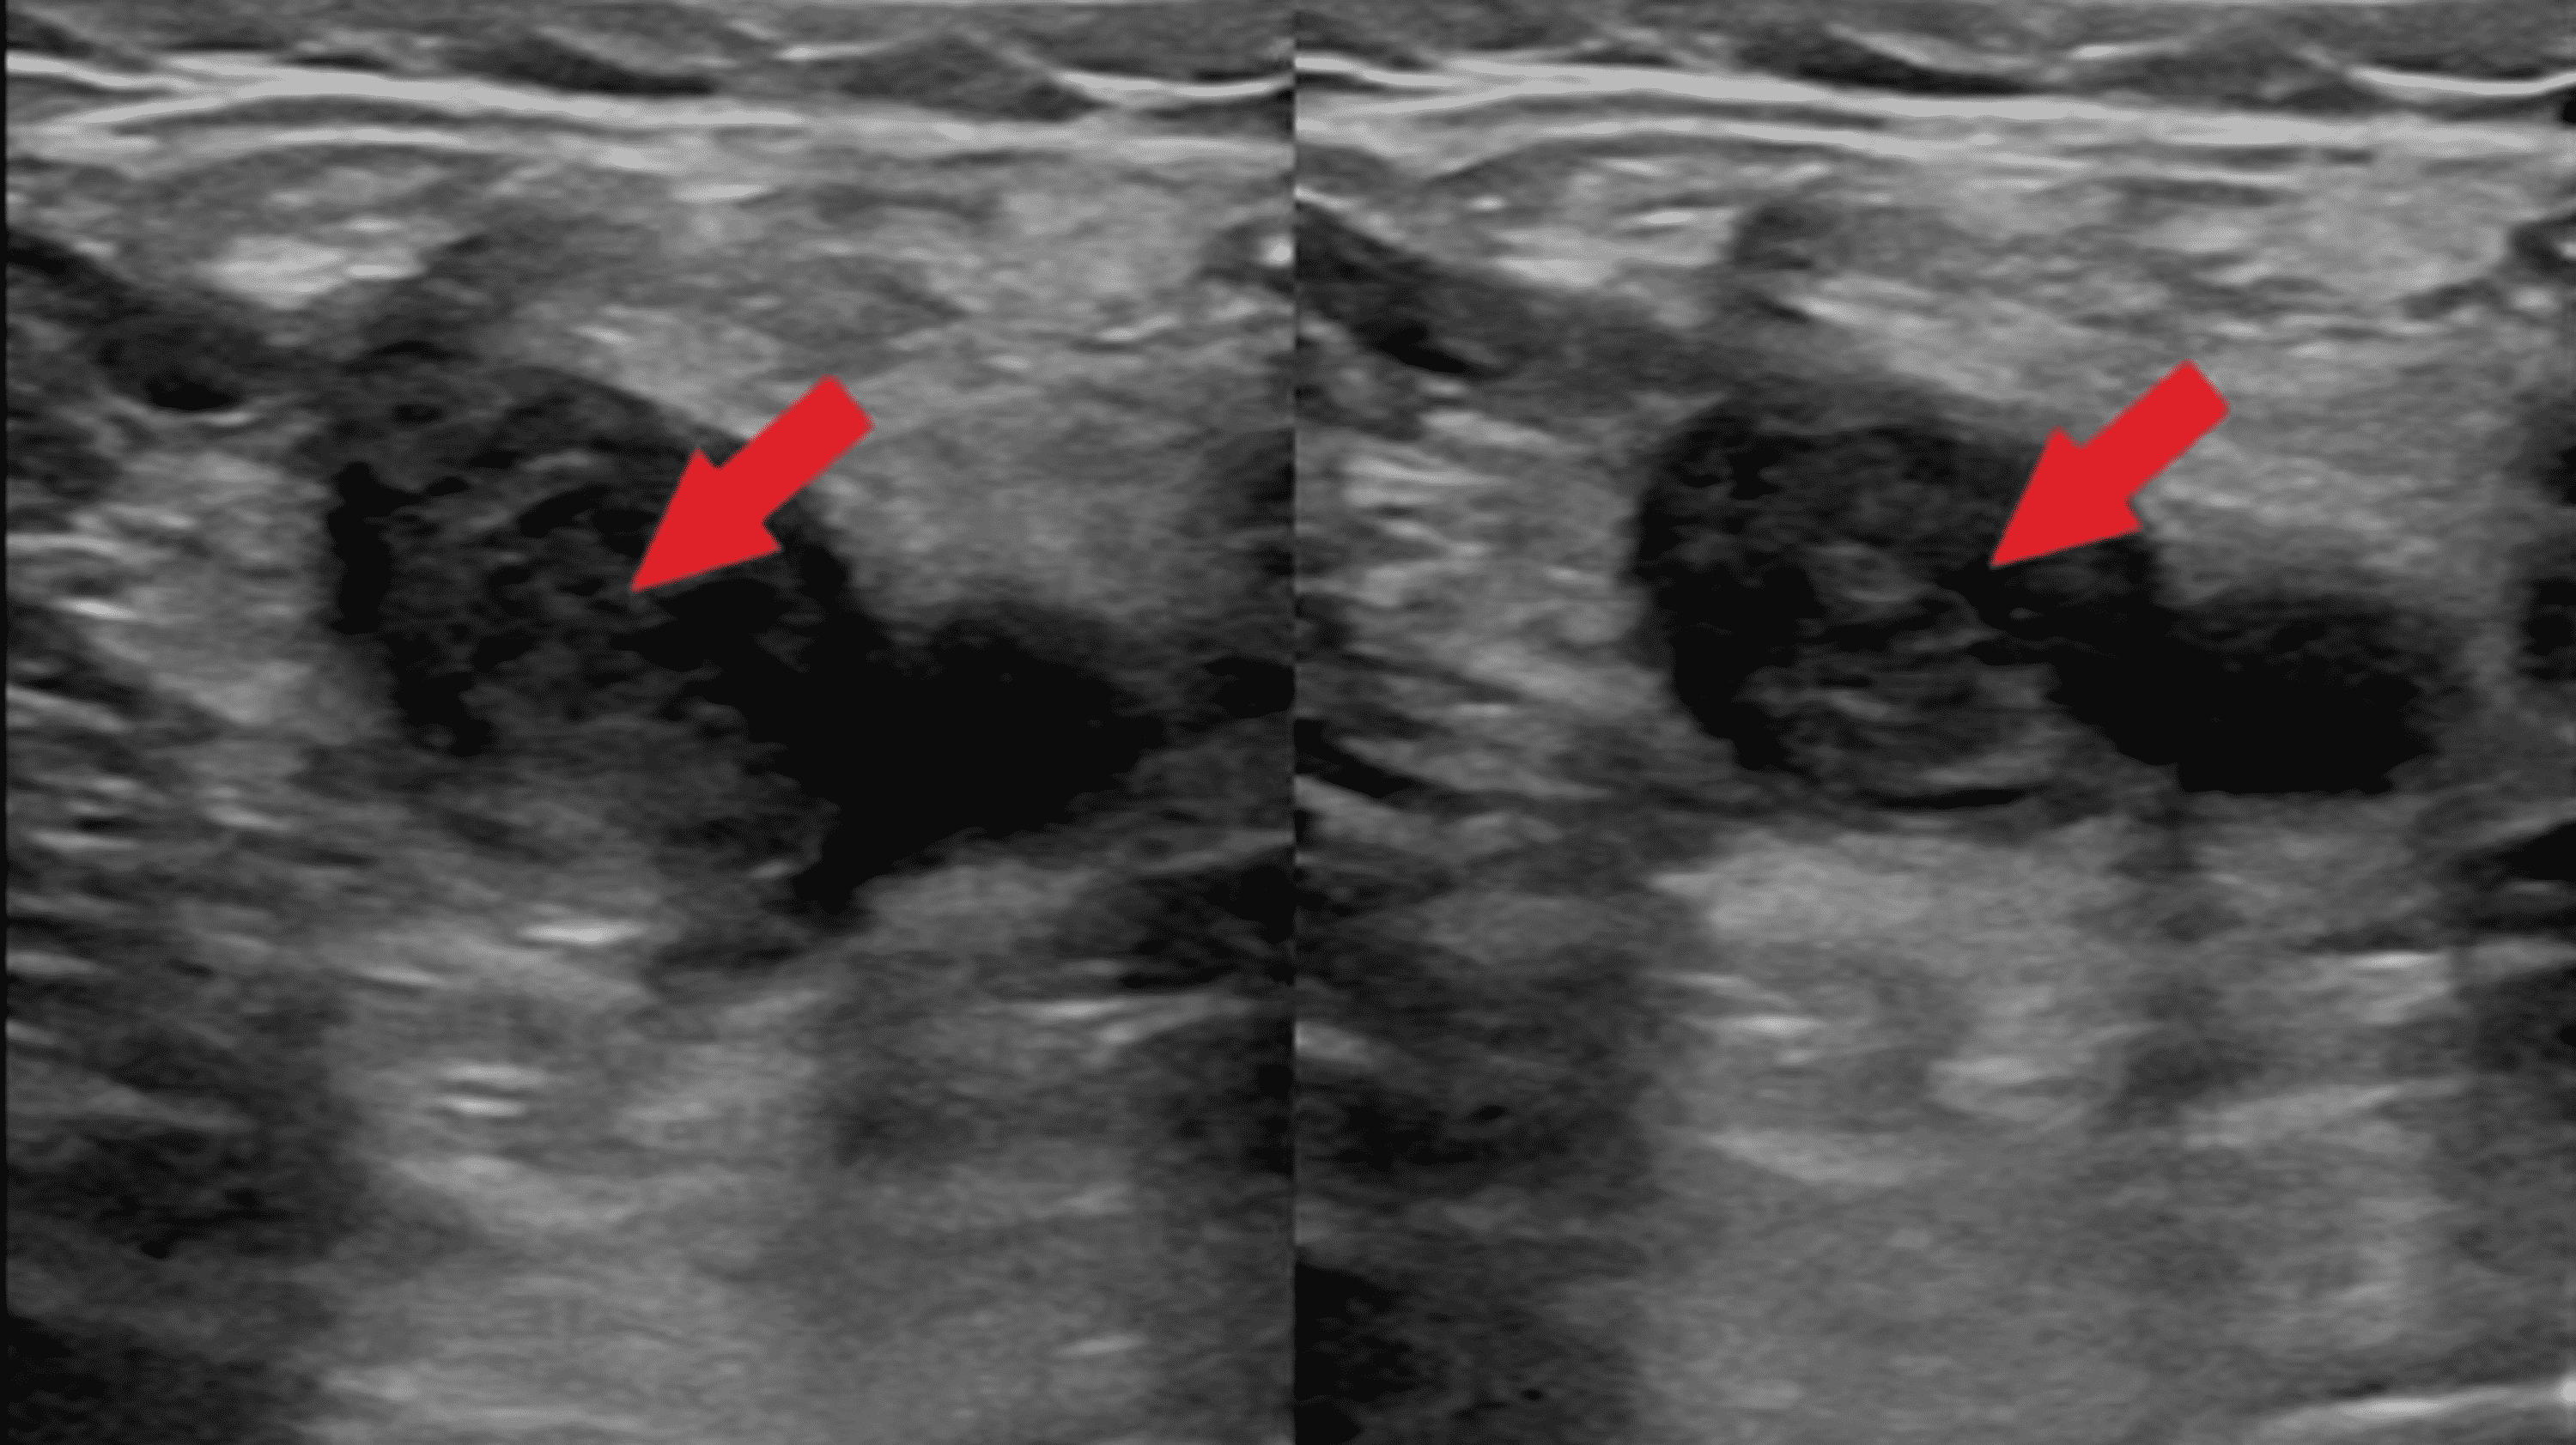

Figure 1 from Thymic Hyperplasia in Graves’ Disease Semantic Scholar Thymic Hyperplasia Graves Ct scans of three subjects with graves’ disease (gd) who had thymic enlargement diagnosed incidentally, showing. Thymic hyperplasia in graves' disease is related to excess thyroid hormones and thyrotropin receptor antibody. Thymic hyperplasia is commonly associated with graves' disease, but it is not emphasized in major endocrinology texts and must be recognized by. Graves’ disease (gd) is an autoimmune condition. Thymic Hyperplasia Graves.